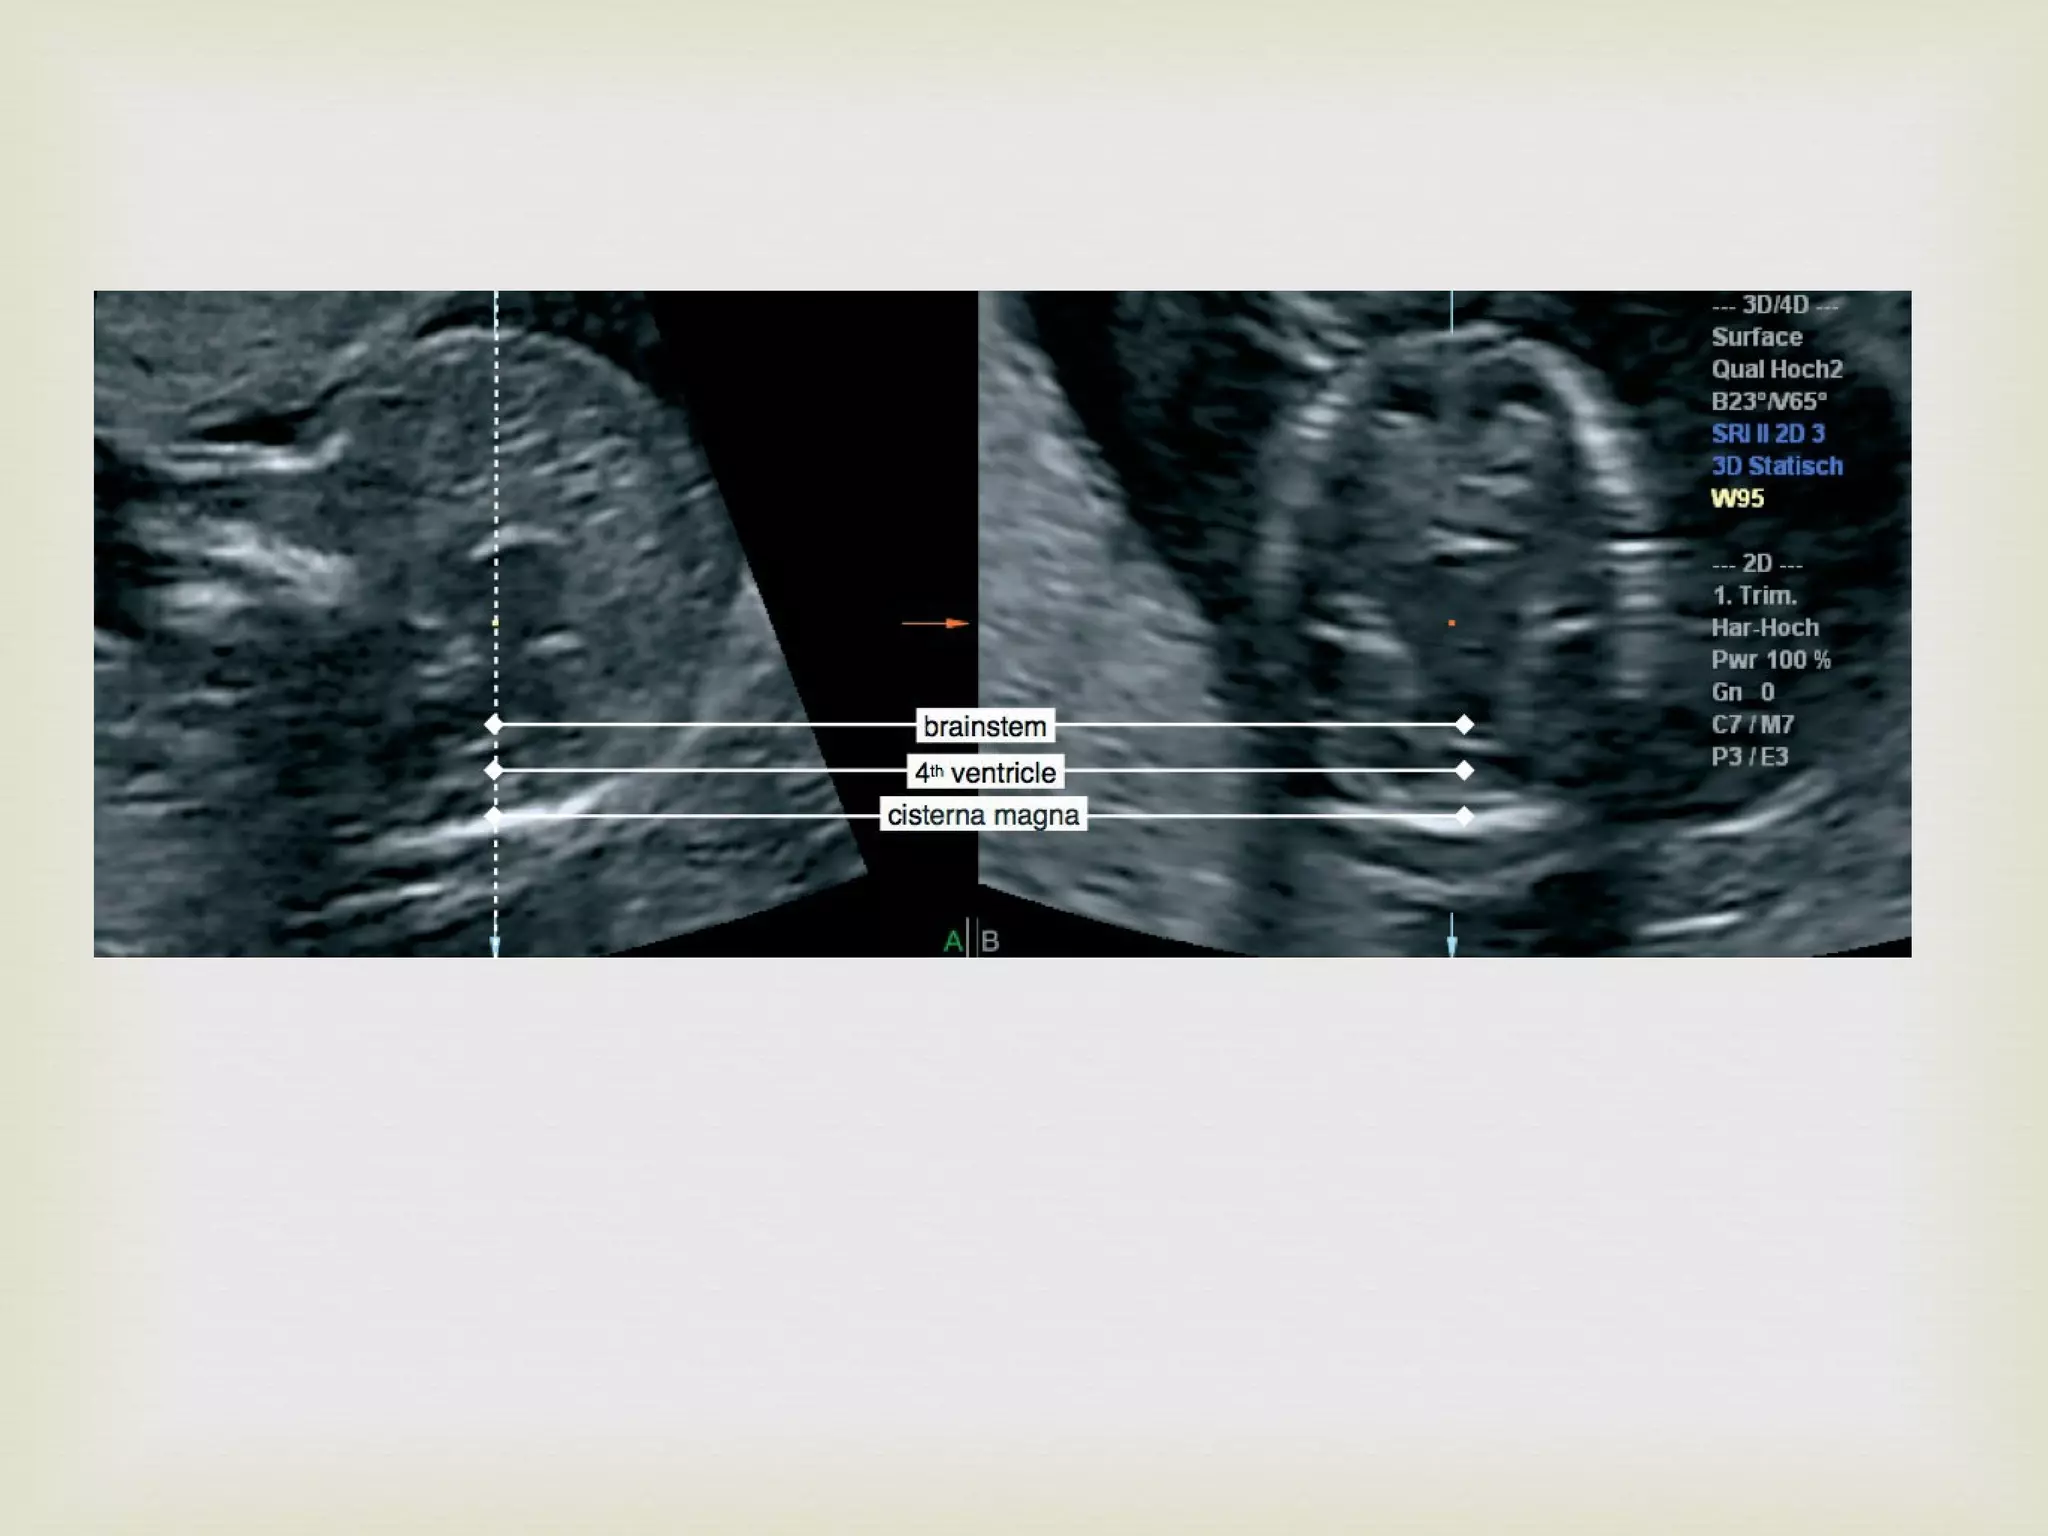

More technological refinement   3D USG

Brain Stem Diameter (BSOB) Brain Stem Occipital Bone Diameter

The underlying mechanism of Lemon and Banana sign is the same that is being used to diagnose open neural tube defect in 11-14 weeks More things change, more they remain the same…